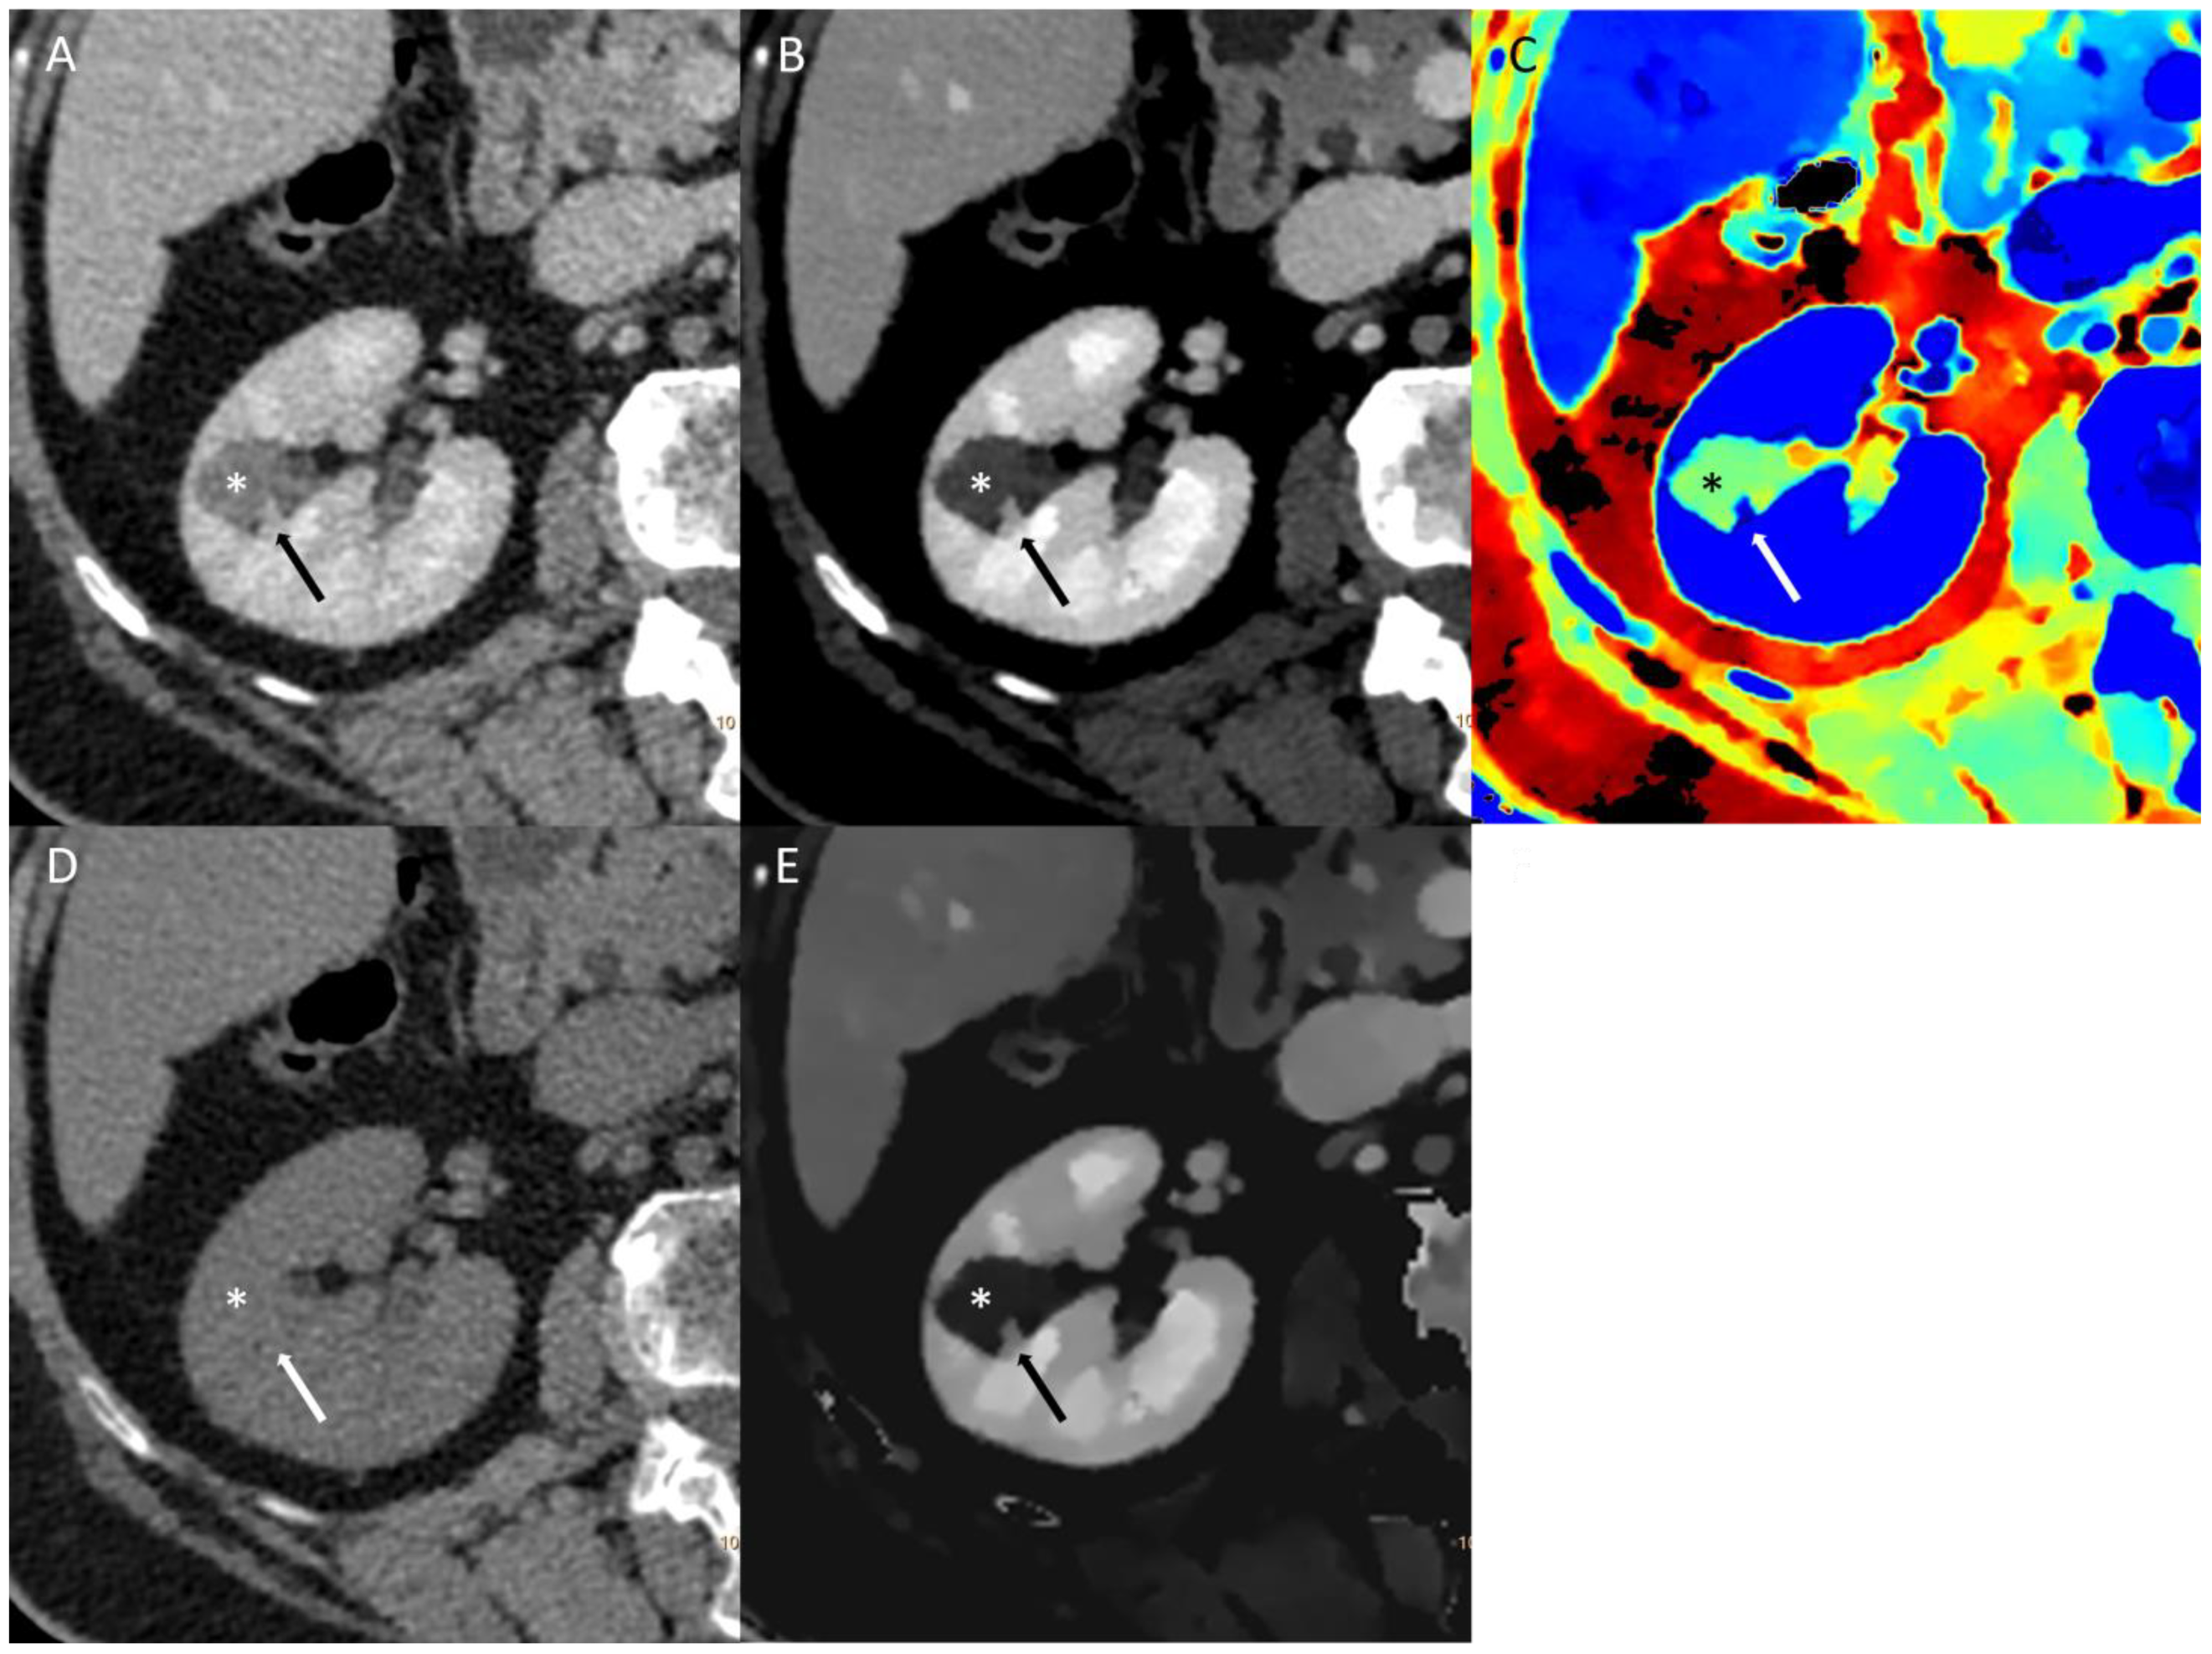

An example of spectral imaging of a bladder lesion can be found in Figure 3.

Figure 3. Conventional multi-energetic CT image in portal venous phase (A) of bladder cancer (*) in comparison with a small area of the healthy bladder wall (arrow). Virtual monoenergetic image (B) shows poor changes in the healthy bladder wall and inhomogeneous enhancement of the cancer. Z-effective maps image (C) shows atomic numbers within the healthy bladder wall and high numbers in cancer. Virtual Non-Contrast image (D) shows poor difference in the densitometry of the healthy bladder wall. Iodine density imaging (E) shows poor iodine concentration in the healthy bladder wall and high iodine concentration in the cancer.